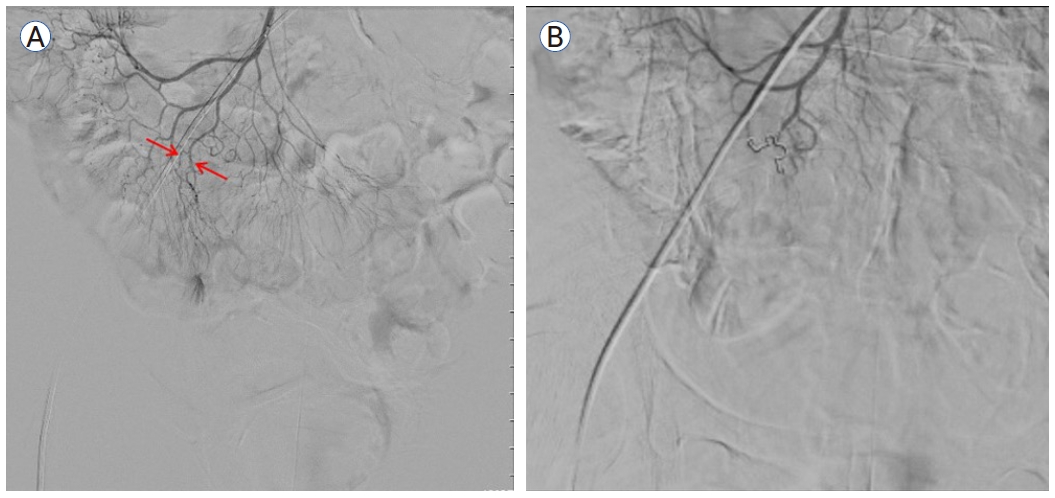

입원 후 시행한 말초 혈액 검사에서 혈색소 수치가 8.4 g/dL로 감소하였으며 이후 이틀간 7.0 g/dL, 5.1 g/dL로 감소하면서 혈변이 지속되어 복용 중인 아스피린, 클로피도그렐을 중단하고 수혈을 진행하였다. 출혈 부위를 찾기 위하여 시행한 상부 위장관 내시경 및 결장경 검사 결과 명확히 출혈을 의심할 만한 부위는 발견되지 않았다. 다음날 추가로 200 g의 혈변이 있어 수혈 후 결장경 검사를 재시행하였으나 출혈 부위를 찾지 못하였다. 이후 복부 출혈 CT 검사를 시행하였고(Fig. 1A) 회장 부위에 출혈 소견이 보여 혈관조영술 검사를 진행하였다(Fig. 1B).

Figure 1.

(A) Transverse contrast-enhanced arterial phase image demonstrate enhancing dot-like structure, which suggested vascular lesions in the ileum. (B) The red arrow indicates extravasation of the contrast dye outlined the ileal mucosa.